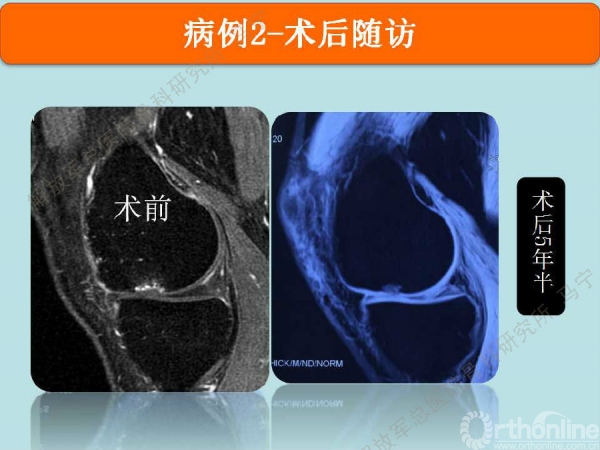

病例2

患者,男,26岁,右膝关节间断性疼痛3年,关节屈曲经过40度时有弹响伴疼痛,发现股骨髁局部软骨缺损。损伤的软骨下骨可见明显水肿。

术后6个月仍能看到修复区的软骨,术后12个月软骨仍在继续修复,修复的厚度满意。

术后5年半,目前膝关节无明显症状。MRI显示修复区的软骨仍有一定的厚度。损伤的软骨区没有继续扩大。